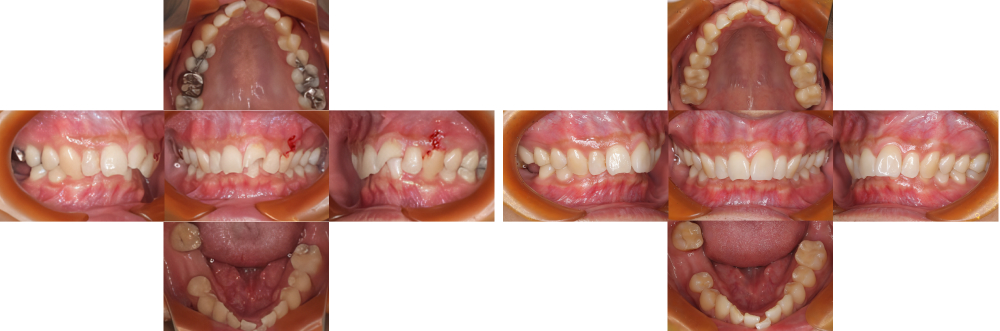

全顎保険治療

術前

術後

| 治療内容 | 全顎的に保険内で治療を行った |

|---|---|

| 治療期間・回数 | 約2.5年・約50回 |

| 費用 | 保険適用となります |

| リスク・副作用 |

|